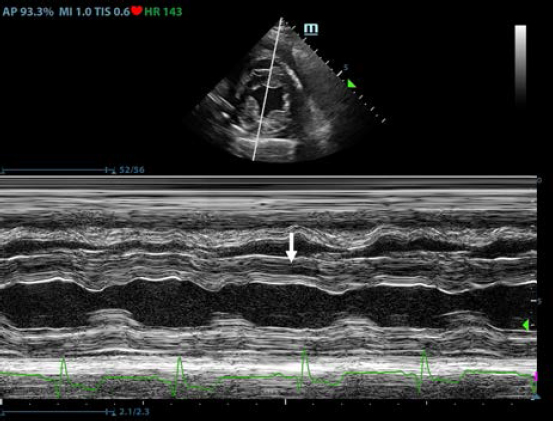

Fig. 3. Transthoracic echocardiogram – M-mode right parasternal short axis view of the left ventricle. Note the paradoxic septal motion (white arrow) characterized by diastolic posterior motion of the interventricular septum toward the left ventricular free wall.

First, transthoracic echocardiogram findings were a small amount of circumferential tamponating pericardial effusion (Fig. 1) and a severe hyperechoic pericardial thickening (10.2 mm) (Fig. 2). The right atrium was normal in size and there was collapse during systole. There was mild septal flattening seen on short axis view of the left ventricle. A short-axis left ventricular M-mode showed posterior displacement of the interventricular septum during late diastole at the time of atrial systole (Fig. 3). The epicardium and pericardium had a hyperechoic appearance with a thin, shaggy layer of heterogeneous echogenic material lining the surface of each (Fig. 1, Supplementary Video I). Pericardiocentesis was not recommended at this time given that the patient was minimally clinically and hemodynamically affected. Few hours later, a second echocardiographic examination, after stabilization of left ventricular volume with intravenous (IV) lactate ringer solution at maintenance rate, showed a worsening of pericardial thickness (13 mm) and an increase in pleural effusion. Furthermore, there was a >25% mitral inflow variation noted with respiration. In addition, there was >30% tricuspid inflow variation with respiration, signs of CP. During the second echocardiography, the patient appeared to be slightly dyspneic due to the increased thoracic effusion.